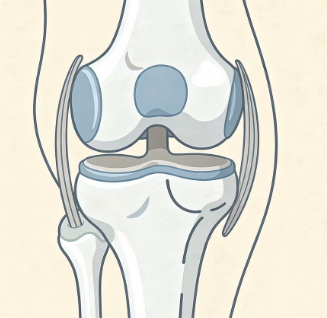

무릎에 물이 찬다는 것은 관절 안에 관절액이 과도하게 증가한 상태를 말합니다.

관절액은 무릎 관절을 보호하고 움직임을 부드럽게 해주는 역할을 합니다.

하지만 염증이나 손상이 생기면 관절을 보호하기 위해 액체가 과다 분비되면서 붓게 됩니다.

즉, 무릎에 물이 차는 것은 관절 내부에 문제가 생겼다는 신호일 수 있습니다.